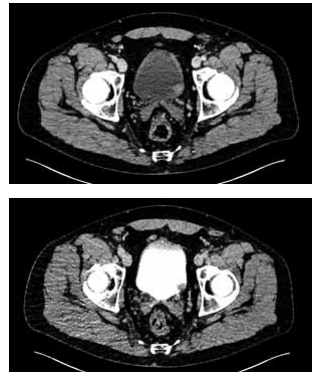

Observe a imagem da tomografia a seguir:

Enunciado 4425227-1

Enunciado 4425227-2

(Arquivo pessoal; imagem usada com autorização)

Qual diagnóstico deve ser considerado com base nos achados da tomografia e qual diagnóstico concomitante está associado à sua hipótese?